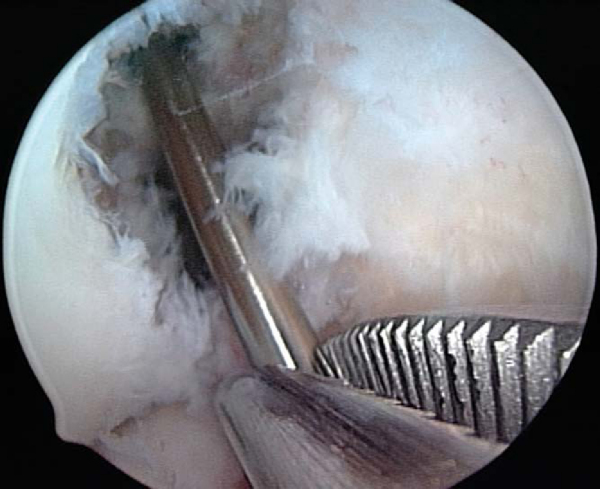

If a metallic screw was used previously for femoral fixation, it may require removal. The surgeon may consider deferment of femoral screw removal until after the new tibial tunnel is made. The bone overgrowth around the screw along with any remaining soft tissue (

Fig. 64-5

) has to be débrided to prevent stripping of the screw. A flexible nitinol pin is placed through the screw, and an appropriate screwdriver is used to remove the old screw. This “technical pearl” may facilitate alignment of the screwdriver more easily within the femoral screw hexagonal recess and reduce the possibility of stripping the screw. If the screw is stripped, commercially available screw extractors may need to be used. Alternatively, when the femoral tunnel is placed too vertically, the screw can be advanced forward and not removed, which creates a medial wall support for the new graft.